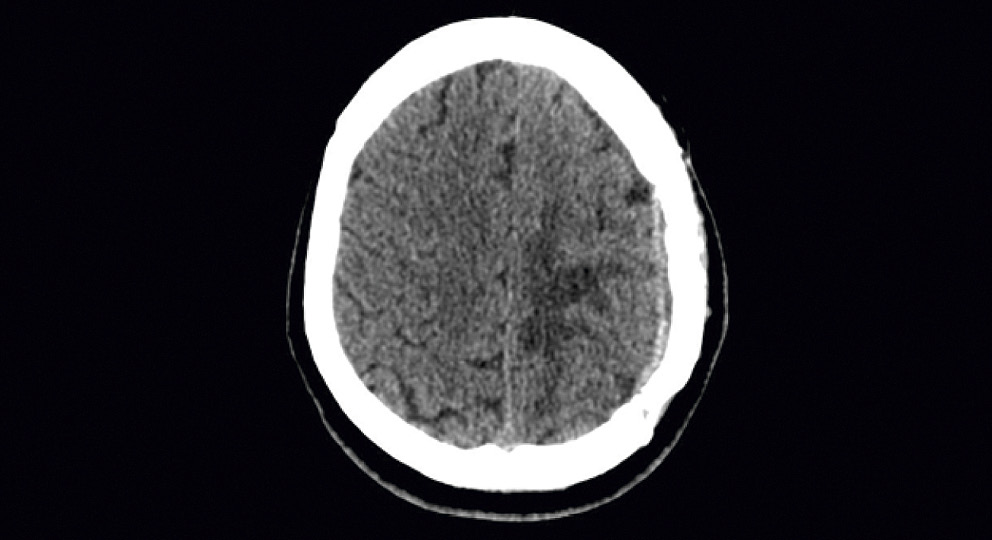

Однако после получения положительных результатов серологических тестов для выявления антител к T. pallidum и спинномозговой (цереброспинальной) жидкости оказалось, что под опухолью головного мозга маскировалась сифилитическая гумма (нейросифилис поздний). После проведенного специфического противосифилитического лечения у пациентки, по данным мультиспиральной компьютерной томографии (МСКТ), отмечалась положительная динамика: уменьшение отека вещества головного мозга и выраженности дислокации срединных структур (рис. 9).

Рис. 9. Результаты МСКТ после противосифилитического лечения (через 6 мес.)

Fig. 9. MSCT findings after antisyphilitic treatment (in 6 months)